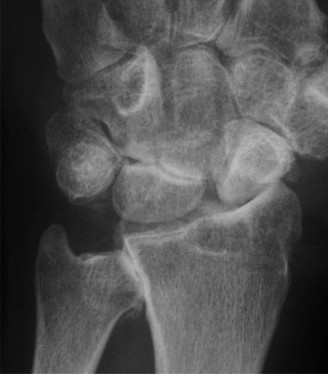

When the scaphoid fractures, this vital mechanical link is disrupted. The distal fragment flexes with the distal carpal row, while the proximal fragment extends with the lunate (due to the intact scapholunate interosseous ligament). This opposing motion results in the classic "humpback" deformity—a volar angular collapse of the scaphoid that alters carpal kinematics, reduces the carpal height, and leads to a dorsal intercalated segment instability (DISI) pattern. Failure to correct this anatomical collapse during surgical fixation inevitably leads to altered contact mechanics, progressive articular wear, and eventual scaphoid non-union advanced collapse (SNAC).

Defining Operative Thresholds

In the adult population, any scaphoid fracture demonstrating greater than 1 mm of displacement is an absolute indication for surgical fixation. Displacement signifies disruption of the cartilaginous envelope and a higher energy injury, correlating with a non-union rate exceeding 50% if treated non-operatively. Furthermore, an intrascaphoid angle greater than 35 degrees or a radiolunate angle greater than 15 degrees indicates a humpback deformity and DISI collapse, respectively, mandating open reduction and internal fixation (ORIF).